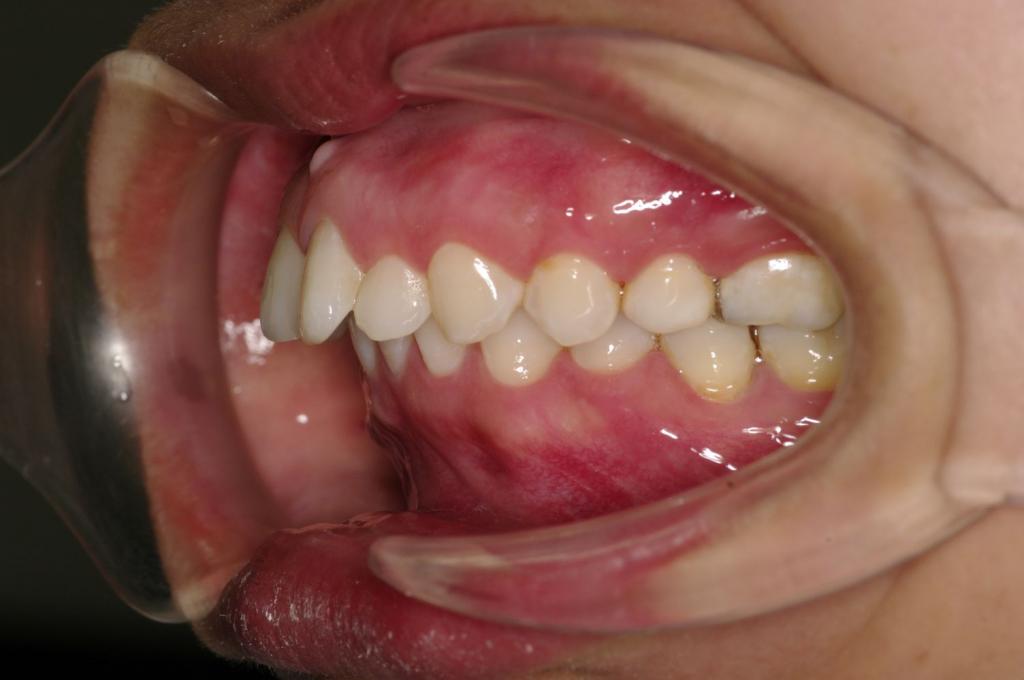

前歯、出っ歯・開咬の矯正治療

(治療期間、治療前後写真、治療方法、費用)WORKS